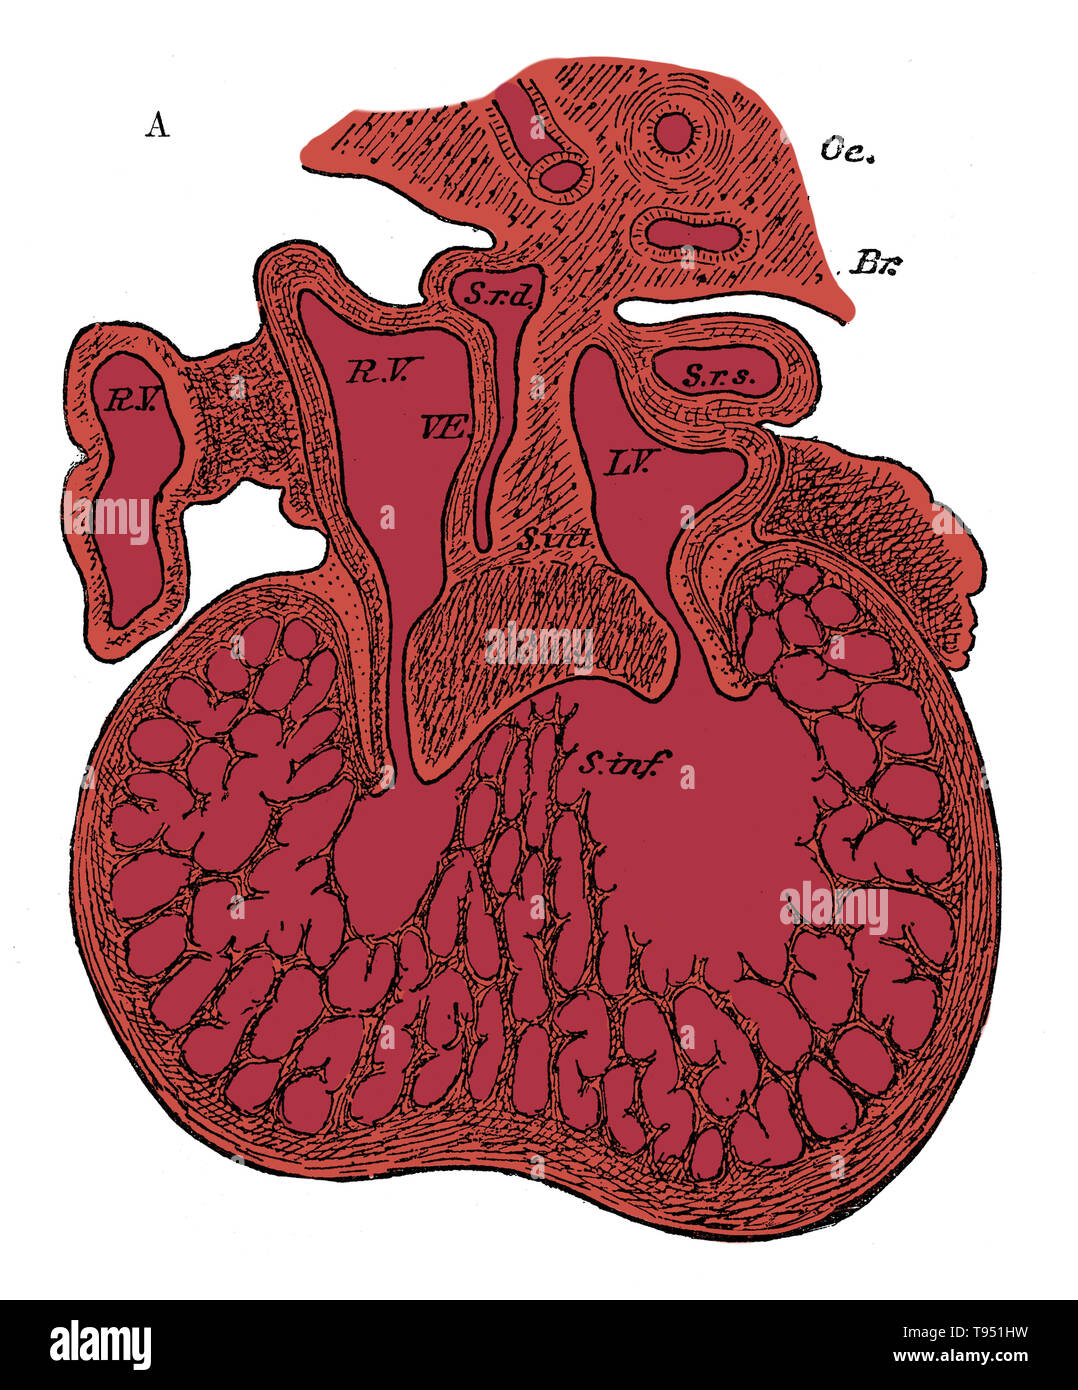

Section through the heart of human embryo showing the formation of the cardiac septa and the auriculo-ventricular valves, 5 to 6 weeks. R.V, right auricle; L.V, left auricle; S.r.d, right horn of sinus; Sr.s, left horn of sinus; s. int, septum superior and endocardial cushion (septum intermedium); s. inf, septum infers ventriculorum; This septum, as well as the bulk of the ventricle, is a muscular sponge at this stage. Oc, esophagus; Br, bronchus. Stock Photohttps://www.alamy.com/image-license-details/?v=1https://www.alamy.com/section-through-the-heart-of-human-embryo-showing-the-formation-of-the-cardiac-septa-and-the-auriculo-ventricular-valves-5-to-6-weeks-rv-right-auricle-lv-left-auricle-srd-right-horn-of-sinus-srs-left-horn-of-sinus-s-int-septum-superior-and-endocardial-cushion-septum-intermedium-s-inf-septum-infers-ventriculorum-this-septum-as-well-as-the-bulk-of-the-ventricle-is-a-muscular-sponge-at-this-stage-oc-esophagus-br-bronchus-image246588101.html

Section through the heart of human embryo showing the formation of the cardiac septa and the auriculo-ventricular valves, 5 to 6 weeks. R.V, right auricle; L.V, left auricle; S.r.d, right horn of sinus; Sr.s, left horn of sinus; s. int, septum superior and endocardial cushion (septum intermedium); s. inf, septum infers ventriculorum; This septum, as well as the bulk of the ventricle, is a muscular sponge at this stage. Oc, esophagus; Br, bronchus. Stock Photohttps://www.alamy.com/image-license-details/?v=1https://www.alamy.com/section-through-the-heart-of-human-embryo-showing-the-formation-of-the-cardiac-septa-and-the-auriculo-ventricular-valves-5-to-6-weeks-rv-right-auricle-lv-left-auricle-srd-right-horn-of-sinus-srs-left-horn-of-sinus-s-int-septum-superior-and-endocardial-cushion-septum-intermedium-s-inf-septum-infers-ventriculorum-this-septum-as-well-as-the-bulk-of-the-ventricle-is-a-muscular-sponge-at-this-stage-oc-esophagus-br-bronchus-image246588101.htmlRMT951HW–Section through the heart of human embryo showing the formation of the cardiac septa and the auriculo-ventricular valves, 5 to 6 weeks. R.V, right auricle; L.V, left auricle; S.r.d, right horn of sinus; Sr.s, left horn of sinus; s. int, septum superior and endocardial cushion (septum intermedium); s. inf, septum infers ventriculorum; This septum, as well as the bulk of the ventricle, is a muscular sponge at this stage. Oc, esophagus; Br, bronchus.